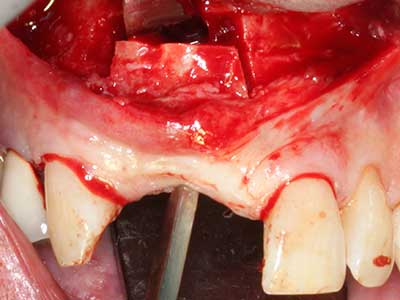

Bei der Knochenblockentnahme zeigen sich weitere Vorteile für die Piezochirurgie: Neben der bereits beschriebenen hohen Präzision bei der Osteotomie stellt sich gerade die Verwendung der dünnen Sägespitzen als besonders materialschonend heraus. Bei der Verwendung insbesondere von Lindemannfräsen sind mit deutlich höheren Entnahmeverlusten durch die dickere Instrumentenspitze zu rechnen (Lakshmiganthan, Gokulanathan et al. 2012). Die insbesondere bei retromolar entnommenen Blocktransplantaten notwendige basale Abtrennung wird durch speziell hierfür vorgesehene rechtwinklige Sägen erleichtert, so dass die Piezochirurgie als präzises, übersichtliches und sicheres Verfahren zur retromolaren Knochenblockgewinnung angesehen wird (Happe 2007) (Abb. 1-12).

Indikation: Bone Splitting